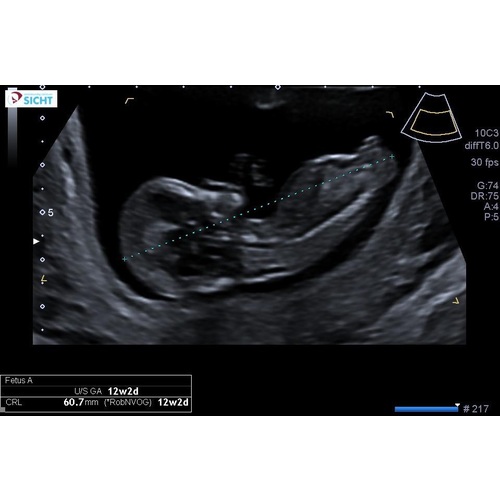

Dit was de 12 weken echo. 🤣ik was ook overtuigd van een jongetje.. het maakt me verder niet zoveel uit, ben al lang blij dat hij/zij in orde lijkt. En die taart lijkt me best lekker 😂😂bedankt voor je felicitatie! 🥰